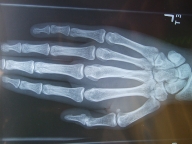

薬指の骨はレントゲンの結果を見れば大丈夫そうなので、なんで動きがおかしいのだろう。

それでレントゲンをもういっかい撮って、骨は前よりくっついているということで安心し、一応骨?手?のスペシャリストに見てもらうことに。

骨折してました...

骨折も脱臼の経験すらなかったので、しかも指も動くしむちゃくちゃ痛くもないので、まさか骨折しているとは思わなかった.

でも完全に折れてるわけではなくて大きなひびが入ったかんじ. 中指.

どうも脱臼ぽくないと思ってたし、間接部じゃなくて手全体が腫れてた感じなので、「そうか折れてたのか」と納得.